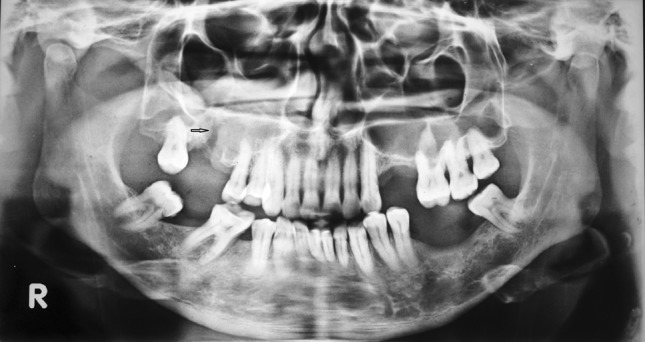

A 50 year old male patient came to the maxillofacial department OP complaining of drainage through the nose while taking water in the mouth. He had undergone extraction of upper right first molar elsewhere, 11 days earlier due to caries. On clinical examination the socket appeared traumatic and margins of the socket were not healed properly and communication to antrum of size 5 × 5 mm was noted (Fig. 1). OPG revealed an oroantral communication at the extraction socket (Fig. 2). PNS view showed generalized haziness of the right antrum which was suggestive of sinusitis (Fig. 3). The treatment plan was to do surgical closure after following proper antral regime and till clear lavage was achieved.

Fig. 2.

OPG showing the communication between maxillary sinus and extraction socket. (Note the arrow)